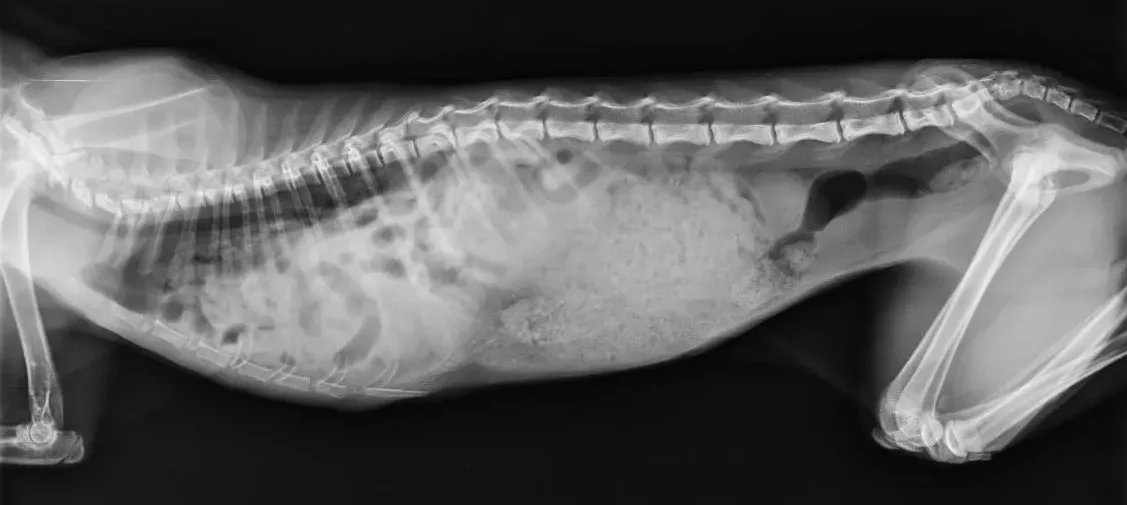

Gato de 5 meses con hernia diafragmática traumática. Se observa contenido abdominal en la cavidad torácica.

• Radiografía de tórax y abdomen: permite ver los órganos desplazados y el contorno del diafragma.